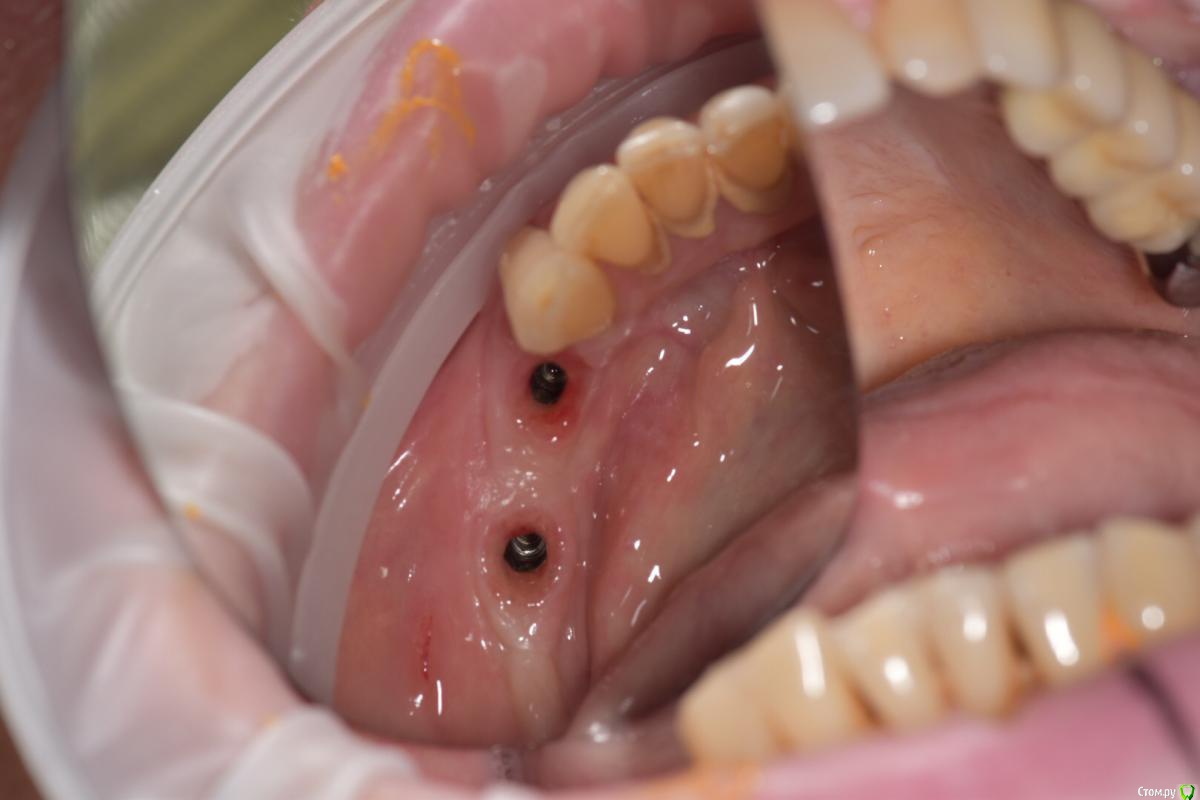

Santi Опубликовано 18 сентября, 2018 Поделиться Опубликовано 18 сентября, 2018 Имеем Концевые деффекты н/ч. Справа по плану НКР+импланты в позициях 4-6, слева импланты+ десна Итог сразу после Через 5-6 месяцев имеем такую картину Сразу после мягкотканной пластики И через пару месяцев Заранее пардоньте за качество фото и отсутствие картины ДО Ваше мнение коллеги ? 3 Ссылка на комментарий

Santi Опубликовано 19 сентября, 2018 Автор Поделиться Опубликовано 19 сентября, 2018 Этапов аугументации к сожалению нету. То , что выложил + этап раскрытия Ссылка на комментарий